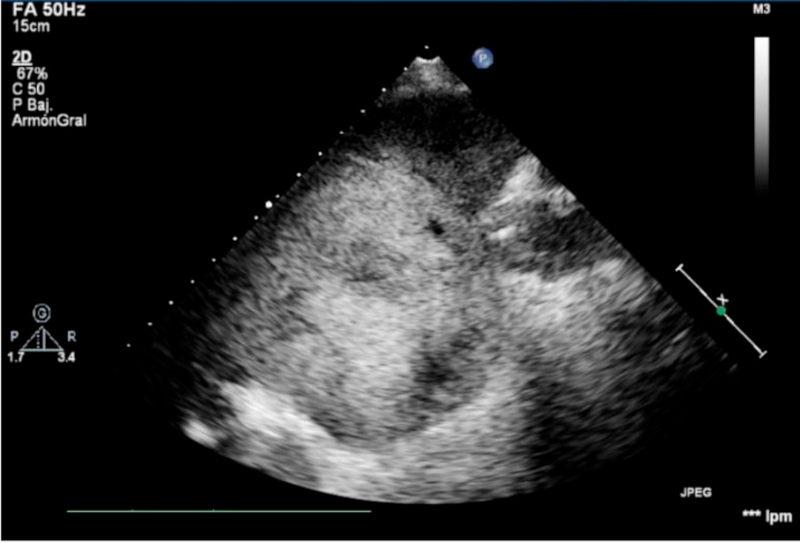

En el ecocardiograma transtorácico: ventrículo izquierdo de dimensiones conservadas, con fracción de eyección 76%, movimiento paradojal del septum interventricular, septum interauricular intacto con relación QP/QS normal; aurícula izquierda de dimensiones conservadas, aurícula derecha dilatada, con presión de 20 mm Hg, ventrículo derecho dilatado con diámetro diastólico de 44 mm y función sistólica normal. Se verifica insuficiencia mitral leve, aparato valvular tricuspídeo hiperecogénico y apertura valvular fija en todo ciclo cardíaco, insuficiencia tricuspídea grave, aumento de la velocidad anterógrada y presión sistólica de la arteria pulmonar estimada de 28 mm Hg.Tronco y ramas pulmonares conservados, insuficiencia pulmonar grave con flujo reverso en ramos pulmonares. Ausencia de masas intracavitarias (Figura 2).